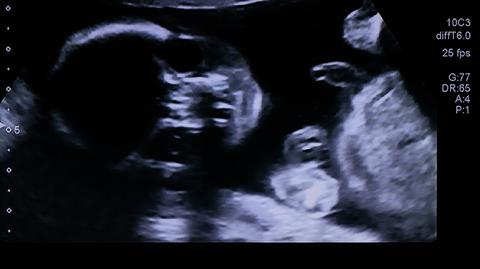

Narażenie na smog może mieć ogromne konsekwencje dla kobiet w ciąży i ich dzieci. Według analiz międzynarodowego zespołu naukowców, cząstki sadzy potrafią przenikać przez łożysko i docierać do narządów nienarodzonych dzieci. To pierwsze badania, które ukazują wpływ zanieczyszczonego powietrza na rozwój płodu.

Zanieczyszczone powietrze może docierać do dzieci znajdujących się w łonach. Dzięki najnowszym analizom badaczy z brytyjskiego Uniwersytetu w Aberdeen i belgijskiego Uniwersytetu w Hasselt, potwierdzono, że nanocząsteczki sadzy - jednej z wielu szkodliwych cząstek emitowanych w wyniku spalania paliw kopalnych - potrafią przenikać przez łożysko i dostawać się do narządów nienarodzonych dzieci.

Eksperci są zdania, że odkrycie jest "szczególnie niepokojące", ponieważ podczas życia płodowego dochodzi do rozwoju kluczowych organów.

By to stwierdzić, przebadano 60 matek wraz z dziećmi z Aberdeen i regionu Grampian w Szkocji. Przeanalizowano także próbki tkanek 36 płodów, które z różnych powodów nie przyszły na świat, a ciąże zostały przerwane między siódmym a 20. tygodniem.

Zespół znalazł dowody na istnienie cząstek sadzy w krwi pępowinowej, co oznacza, że mogą one z łatwością przenikać przez łożysko. Były obecne u wszystkich matek i noworodków, a ich poziom był związany z ilością zanieczyszczeń powietrza, na które dana kobieta była narażona w czasie trwania ciąży. W przypadku płodów, które się nie urodziły, cząstki obecne były w wątrobach, płucach i mózgach. Cząstki znaleziono we wszystkich analizowanych próbkach.

Naukowcy ostrzegli, że cząstki sadzy mogą być widoczne już u dzieci w pierwszym trymestrze ciąży.

To pierwszy raz, kiedy wykazano, że zanieczyszczenia powietrza bezpośrednio dotykają rozwijające się płody.

"Stwierdziliśmy, że wdychane przez matkę cząstki sadzy pochodzące z zanieczyszczonego powietrza mogą przenikać łożysko, a następnie gromadzić się w organach dziecka w czasie ciąży. Ustalenia są szczególnie niepokojące, ponieważ ten etap jest kluczowy dla rozwoju organów" - napisali autorzy w czasopiśmie "Lancet Planetary Health".

- Wiemy, że narażenie na zanieczyszczenia powietrza w czasie ciąży i niemowlęctwa zostało powiązane z poronieniami, przedwczesnym porodem, niską wagą niemowląt i zaburzonym rozwojem mózgu oraz z konsekwencjami, które utrzymują się przez całe życie. W tym badaniu pokazujemy, że liczba cząstek sadzy, które przedostają się do ciała matki, jest przekazywana proporcjonalnie do łożyska i do dziecka - skomentował profesor Tim Nawrot, jeden z autorów badania.

- Wszyscy martwiliśmy się, że jeśli nanocząsteczki zanieczyszczonego powietrza dostają się do płodu, mogą bezpośrednio wpływać na jego rozwój w łonie matki. Pierwszy raz pokazaliśmy, że nie tylko potrafią przenikać do łożyska w pierwszym i drugim trymestrze, ale znajdują też drogę do organów rozwijającego się płodu, w tym do wątroby i płuc - dodał Paul Fowler, który także brał udział w badaniach. - Jeszcze bardziej niepokojące jest to, że sadza dostaje się również do rozwijającego się mózgu, co może oznaczać, że oddziałuje na systemy kontroli narządów i komórek płodu - podsumował.